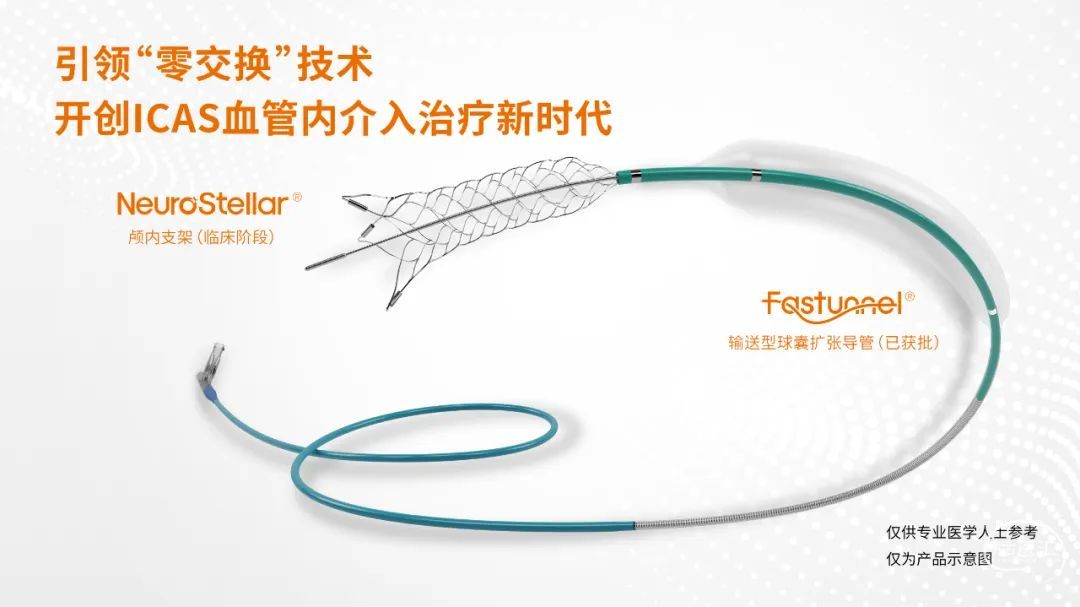

加奇生物Fastunnel®输送型球囊扩张导管是“球囊+微导管”一体化设计,减少了器械交换,提高了手术安全。材质是Pebax半顺应球囊,稳定成形,安全扩张。还具有全程是不锈钢加强结构,提高跟踪性,易于颅内支架输送。